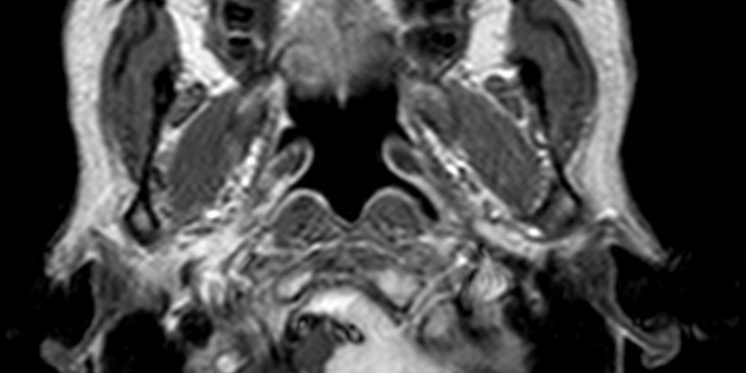

Ο προεγχειρητικός έλεγχος ανέδειξε μηνιγγίωμα της κρανιοαυχενικής συμβολής με εγκολεασμό σημαντικών αγγειακών και νευρικών δομών και επέκταση προς την αντίθετη πλευρά.

Η μετεγχειρητική μαγνητική τομογραφία εγκεφάλου δείχνει ένα εξαιρετικό αποτέλεσμα, με πλήρη αφαίρεση της βλάβης. Η ιστολογική εξέταση επιβεβαίωσε τη διάγνωση (μηνιγγίωμα WHO I).